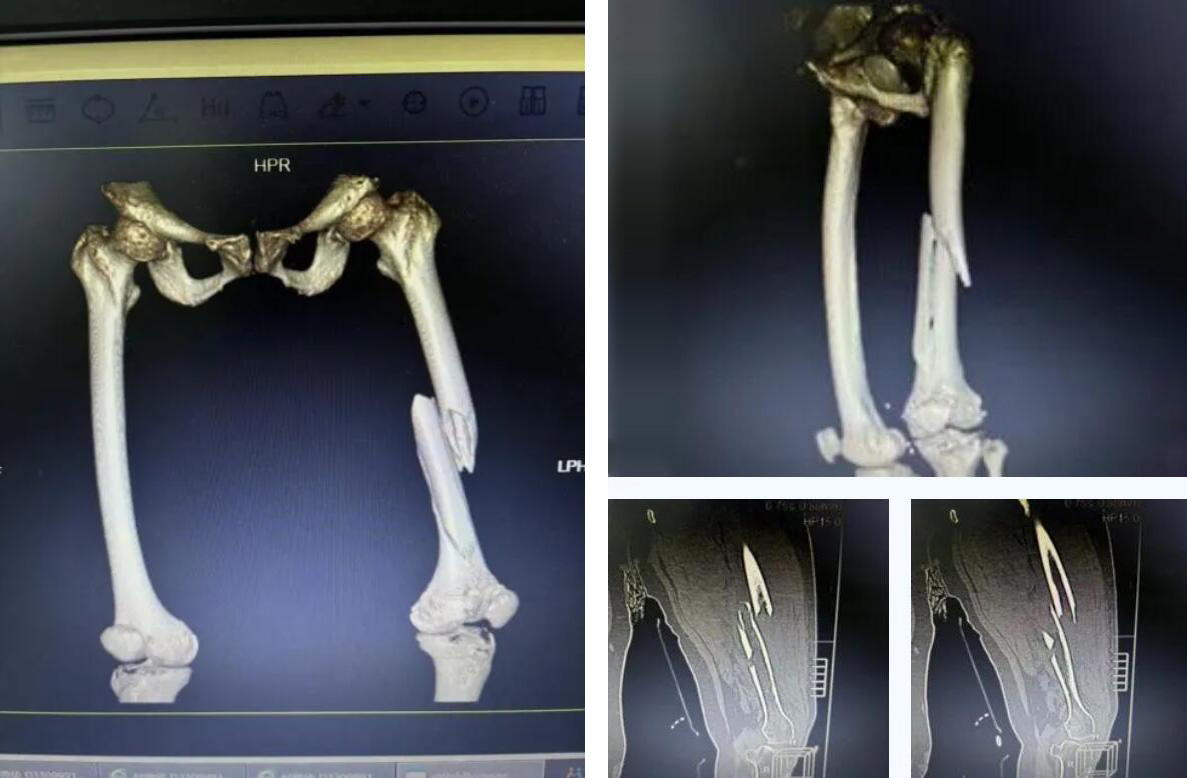

术前患者骨折CT影像

经检查确诊为 “右股骨多段粉碎性骨折”。考虑到俞奶奶年事已高,身体机能衰退,当地医院认为手术风险极大,建议转院治疗。

股骨,即人体的大腿骨,是全身最长的骨骼,对于高龄老人,尤其是超过90岁的超高龄老人而言,髋部骨折常被称为“人生最后一次骨折”,死亡率极高。

而俞奶奶的股骨中段的多段骨折,手术难度和风险更是呈几何级数增加,传统的开放手术创伤大、出血多,老人脆弱的心肺功能难以承受。